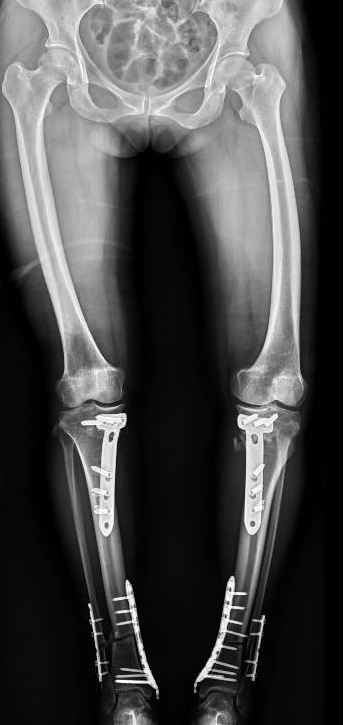

李彬在詳細(xì)了解了董阿姨的病史、進(jìn)行了全面的體格檢查和相關(guān)的輔助檢查后,組織科室進(jìn)行了深入的討論。最終的“答案”是——雙膝骨性關(guān)節(jié)炎、雙膝關(guān)節(jié)畸形、骨質(zhì)疏松以及雙膝半月板損傷。

面對(duì)這樣復(fù)雜且嚴(yán)重的病情,李彬并沒有退縮。他深知,對(duì)于董阿姨來說,這不僅僅是一次手術(shù),更是一次重生的機(jī)會(huì)。因此,他精心制定了手術(shù)方案:對(duì)雙下肢脛骨近端、遠(yuǎn)端以及雙側(cè)腓骨遠(yuǎn)端進(jìn)行截骨矯形,并進(jìn)行植骨內(nèi)固定。這樣的手術(shù)方案,無疑是對(duì)醫(yī)生技術(shù)的一次高難度挑戰(zhàn)!

手術(shù)前 手術(shù)后

2024年8月13日,手術(shù)順利進(jìn)行。

手術(shù)很成功!經(jīng)過精心的治療和護(hù)理,董阿姨在9月順利出院。當(dāng)她再次站在鏡前時(shí),她驚喜地發(fā)現(xiàn)自己仿佛長(zhǎng)高了一截,那份曾經(jīng)讓她備受折磨的疼痛與不適也逐漸消失了。